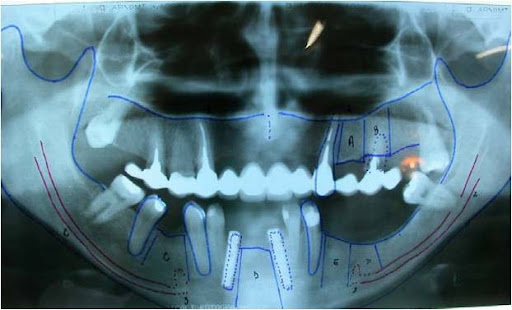

No pós-operatório são prescritas as orientações com o ferimento cirúrgico, antibioticoterapia, antiinflamatórios e analgésicos. São avaliadas periodicamente as alterações sensoriais e sua evolução, além dos controles radiográficos dos implantes (Fig. 14).

Fig. 14 - Controle radiográfico ortopantomográfico dos implantes e da alteração na anatomia mandibular.

O tempo de carga dos implantes normalmente é postergado para 6 a 8 meses após a fixação dos implantes (10), devido à remoção de estrutura óssea na região entre as corticais superior e basal (Figs. 15, 16 e 17).